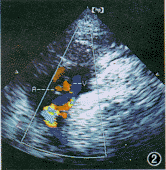

1.脐血流变化:我们观察到脐带血流有几种形态变化,基本上分为3类型。(1)“川”字形(图1);$形(图2)。多数这两种形态并存,并在同一切面上,脐静脉几乎呈直线状,动脉与静脉显示的长度不一致。(2) 扭麻绳状(图3),这种形态少见,且在1个切面上动脉与静脉长度显示几乎相等排列。既脐静脉不能直线行走,与动脉血流呈间断显示。

图2 脐带血流呈“$”形,静脉呈直线状